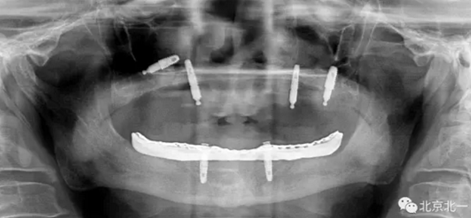

圖一:球帽覆蓋義齒

1.png